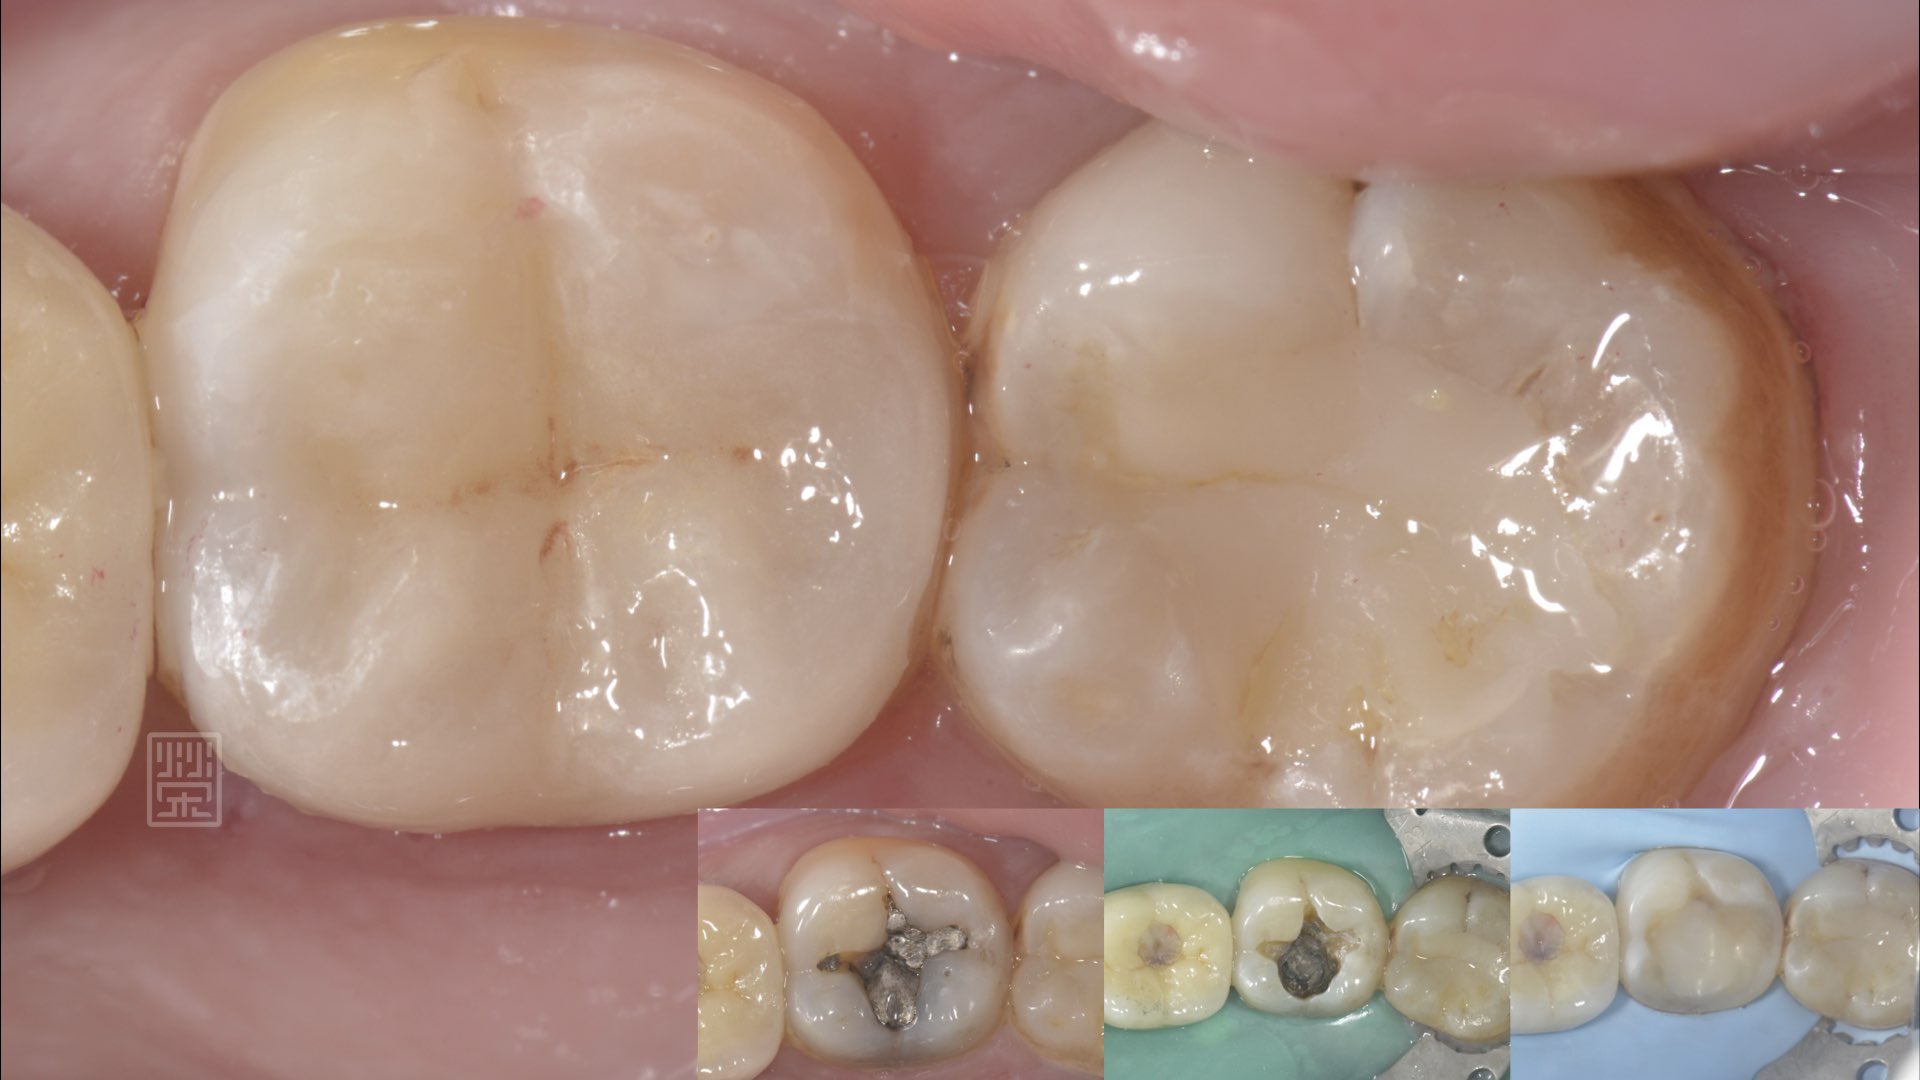

銀粉破裂

牙齒裂痕